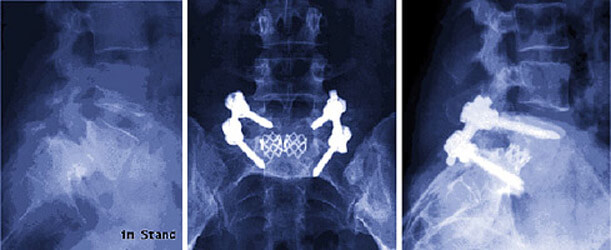

Das rechts stehende Bild ist die konventionelle Röntgenaufnahme eines Wirbelgleitens zwischen den Wirbeln 4 und 5 der Lendenwirbelsäule. Der Schweregrad liegt auf der Grenze zwischen dem Stadium 1 und 2. Im Bild ist die unterbrochene Interartikularportion zu sehen, ohne diesen Defekt kann es nicht zum Gleiten kommen. Dieser Defekt der Interartikularportion wird Spondylolysis genannt. Das kann angeboren sein, aber auch durch zunehmenden Verschleiß der Bandscheiben erworben werden. Dann spricht man von einer Pseudospondylolisthese (erworbenes Wirbelgleiten).

Man muss den nach vorn oder hinten versetzten Wirbelkörper zur richtigen Ausgangsstellung zurücksetzen (man spricht von der sog. Reposition). Anschließend muss mittels Schrauben die richtige Position abgesichert werden. Man kann diesen Eingriff in verschiedenen Möglichkeiten ausführen. Oftmals bietet es sich an die Operation von vorne und hinten durchzuführen, in vielen Fällen wird aber auch ein sehr gutes Ergebnis bei ausschließlicher Stabilisierung von hinten ohne öffnung des Bauchraumes durch eine sog. PLIF-Methode erreicht.

Bilder zu Wirbelgleiten / Wirbelinstabilität